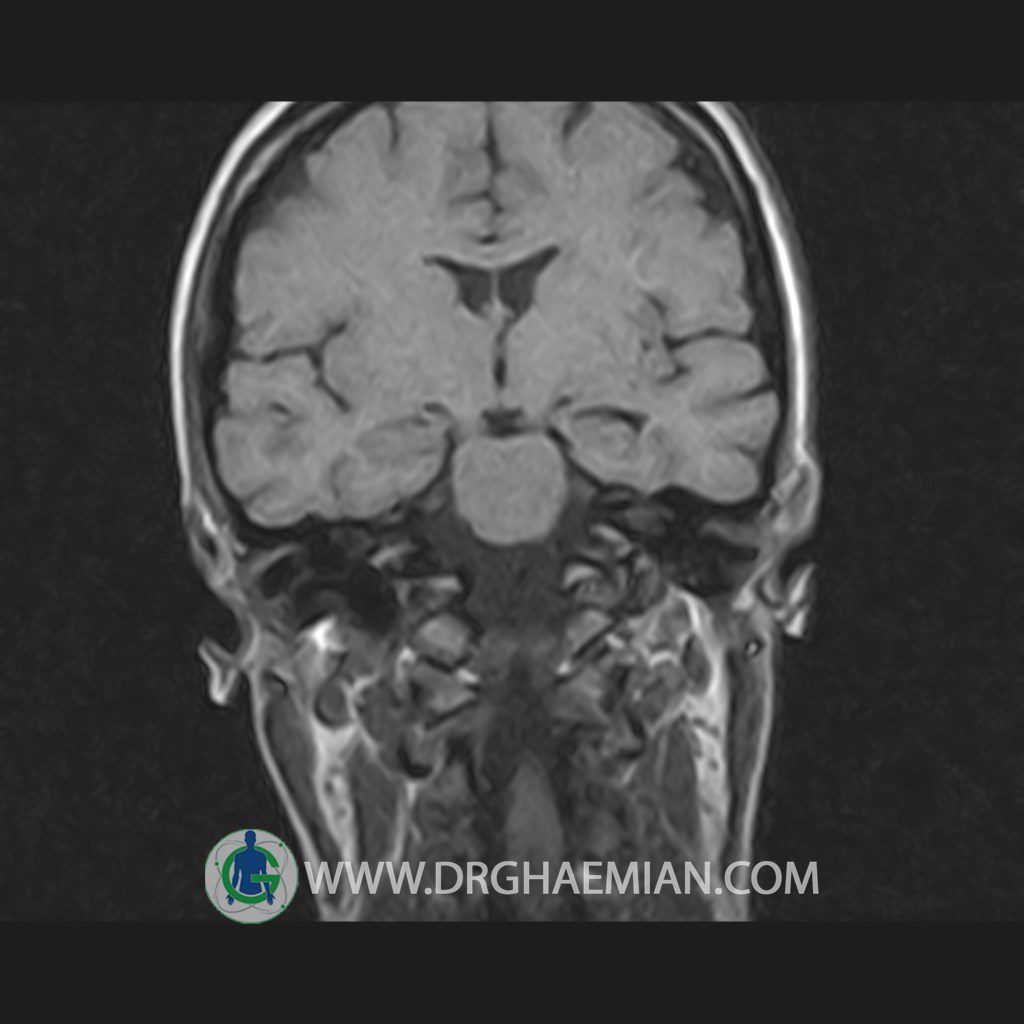

پزشکان اغلب از تصویربرداری ام آر آی برای تشخیص و درمان عارضه های پزشکی که فقط با استفاده از اشعه ایکس یا میدان مغناطیسی و امواج رادیویی قابل مشاهده است، استفاده می کنند. دستگاه ام آر آی تصاویر دقیق از ساختار های داخلی بدن ایجاد می کند. در این کیس هیپرپلازی هیپوفیز و آدنوم مشاهده می شود.

HYPOPHYSIS MRI

(with and without contrast)

Technique: Axial , coronal T1 , Axial , coronal , sagittal T2 , Axial, coronal T1 post Gd & 64 dynamic thin coronal slices.

REPORT :

The sella shows normal size , position and configuration .

The borders of its floor and walls are smooth and sharply defined .

The infundibulum is centered and of normal size .

The optic chiasm and suprasellar spaces appear normal .

The cavernous sinus and imaged portions of the internal carotid artery and carotid siphon are unremarkable .

Evaluable portions of the neurocranium show no abnormalities .

The sphenoid sinus is clear and pneumatized .

– Mild convexity at superior border of pituitary gland with post contrast homogeneous enhancement suggestive for pituitary hyperplasia & iso signal adenoma

is seen